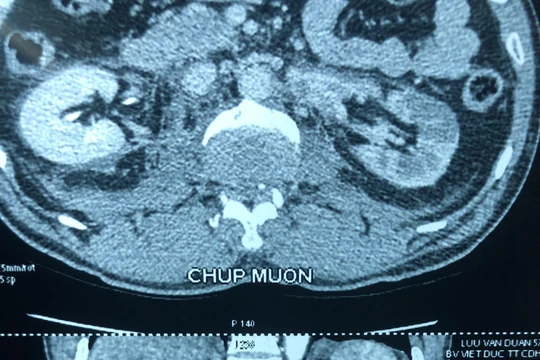

Phim chụp trước mổ của bệnh nhân D. (Ảnh: Bệnh viện Hữu nghị Việt Đức)

Ghép thận tự thân thành công dù bệnh nhân đã bỏ lỡ “thời gian vàng”, nhờ kỹ thuật hiện đại

VietTimes – Người đàn ông 57 tuổi bị suy thận đã bỏ lỡ "thời gian vàng" sau tai nạn xe máy, đã vừa được các bác sĩ của Bệnh viện Hữu nghị Việt Đức cứu sống bằng các kỹ thuật hiện đại để ghép thận tự thân.